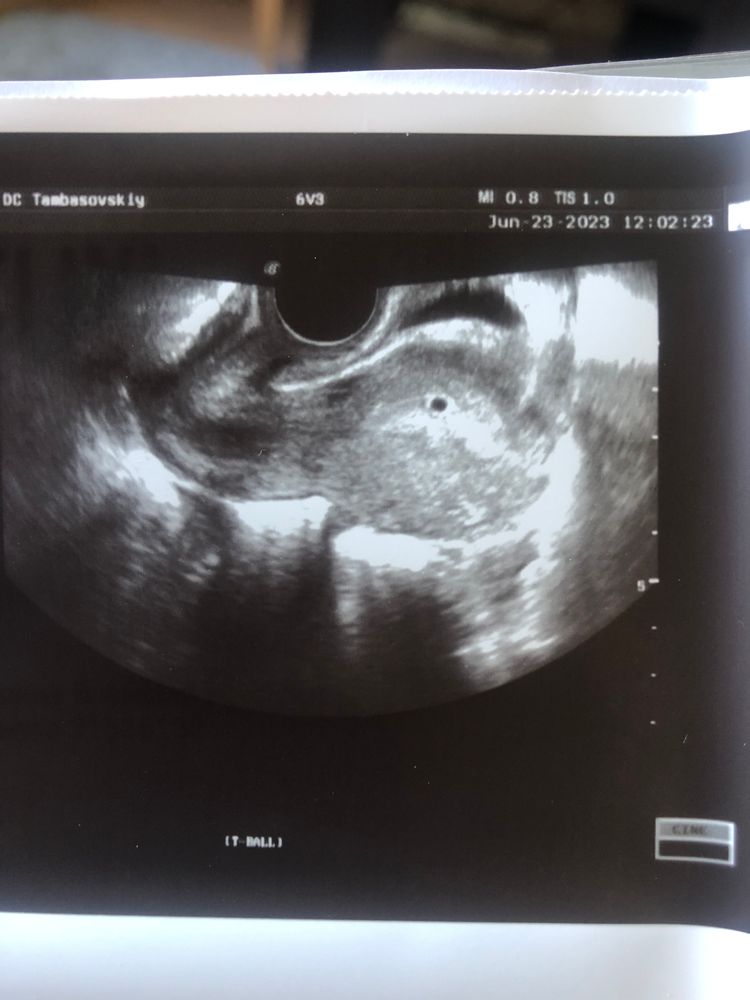

Наше первое узи)

Примите поздравления!!! 🌸 Растите и развивайтесь! Шикарная горошинка ☺️